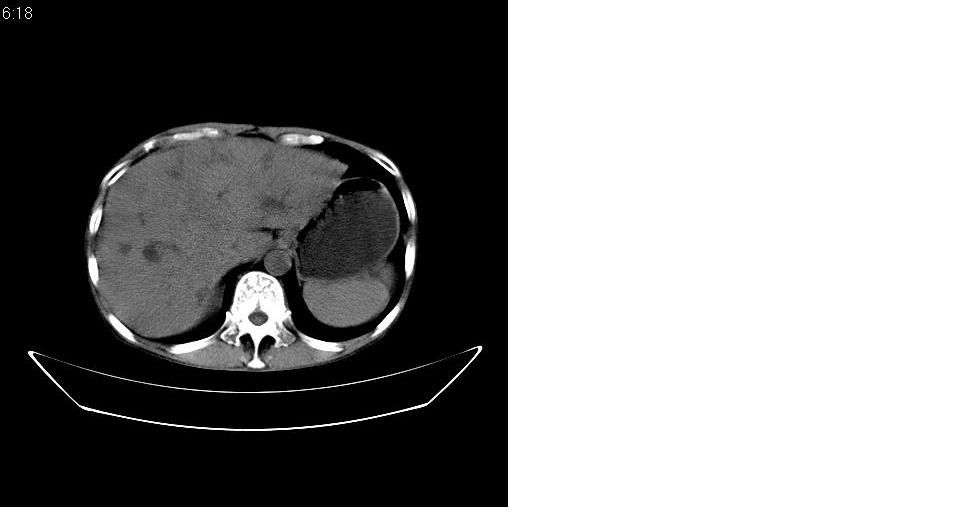

男 55岁,黄染二十余天,无明显腹疼及发热,病人拒绝增强,因没钱.

考虑壶腹周围ca办阻塞性胆道系统扩张、肝转移。 强烈要求增强!

考虑胰头ca伴阻塞性胆道系统扩张、肝转移。建议增强!

考虑胰头癌伴肝门部淋巴结转移及胆管扩张或是肝门部胆管癌伴胰头周围淋巴结转移.

考虑胰头癌伴肝门部淋巴结转移、肝脏转移及胆管扩张。

胰头增大,密度稍低,胰腺体尾部缩小,肝内胆管明显扩张,肝右叶低密度影。 考虑胰头癌并阻塞性肝内胆管扩张,肝内转移灶?建议进一步增强扫描。